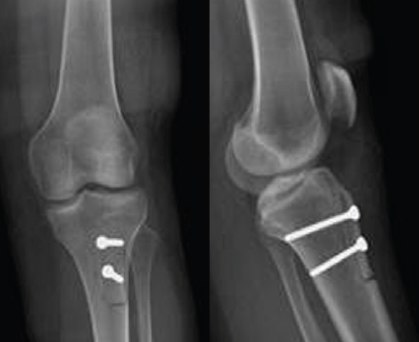

Medial Hoffa’s Fracture Treated with Subvastus Approach – Case Series

Parimal Vairagade , Akhilesh Khobragade , Devashis Barick , Kunal Parmar , Darshan Sharma , Shrikrishna Rakhunde ………………………………p.141-145